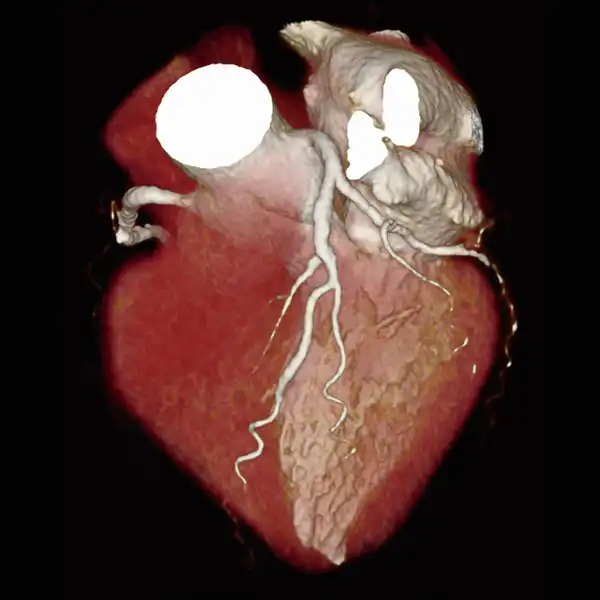

GENESIS Edition’s 16 cm wide area detector signicantly improves your ability to obtain high-quality images for routine and advanced studies. One rotation is all it takes to acquire a whole heart, a neonatal chest, a foot or an ankle exam – in a fraction of a second with less dose and great z-axis uniformity.

Adding dynamic functional imaging to morphology can provide valuable further insights, helping you to optimize disease management and treatment plans. Advanced perfusion maps can assist in diagnosis and therapy response verification of stroke or tumors, while dynamic joint studies help identify causes of pain or immobility.